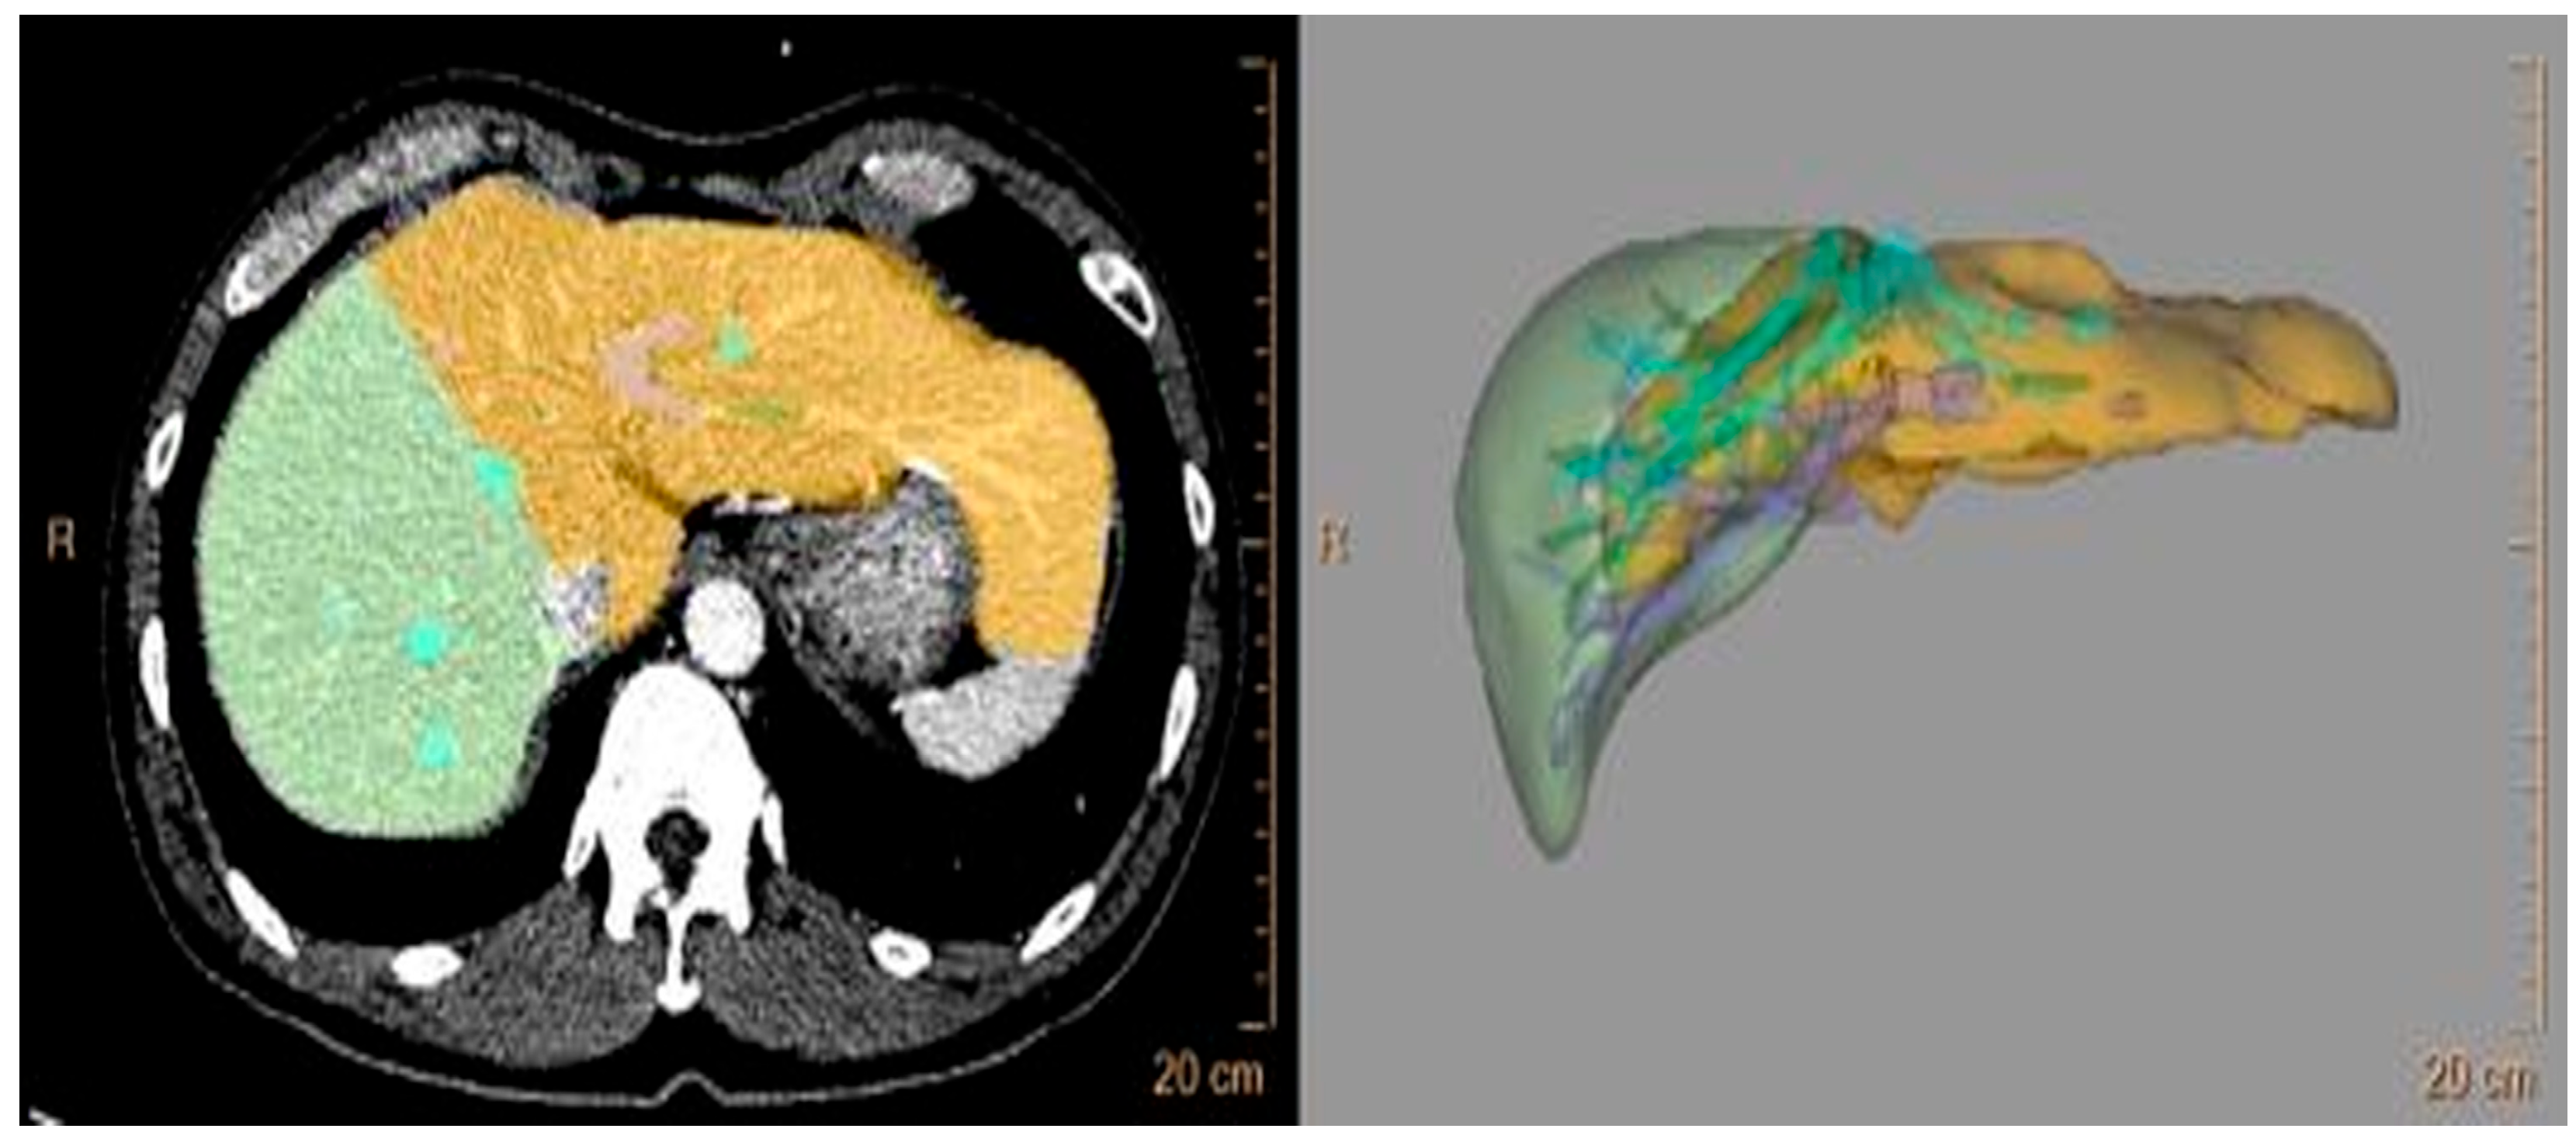

3.1. Correlation between the Estimated GV and Actual Graft Weight